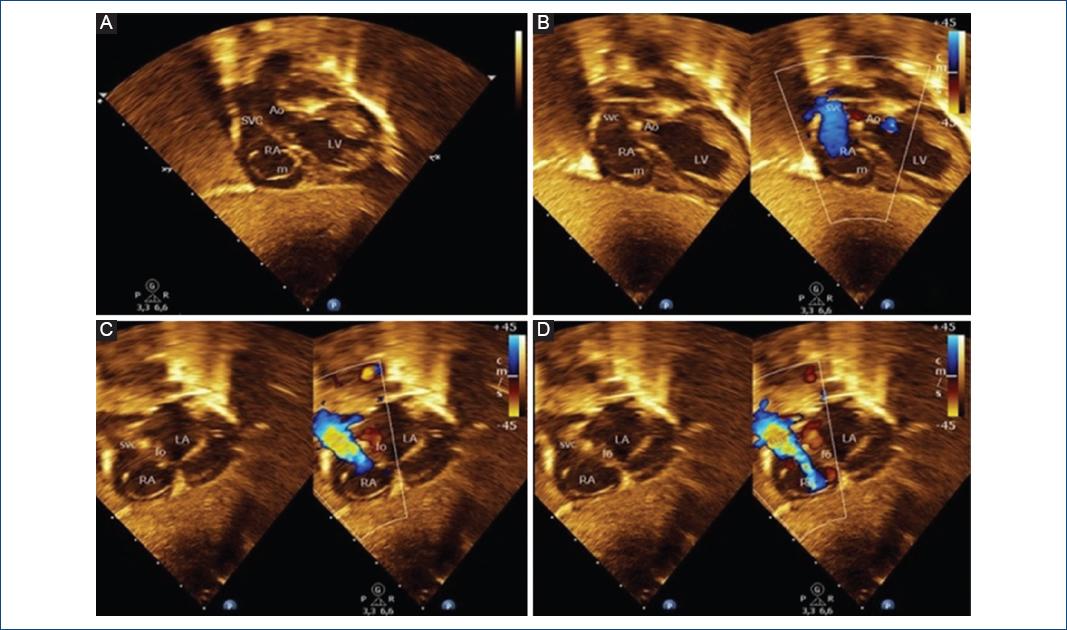

We present the case of a term newborn, with no significant perinatal history, who was taken to the emergency room at 18 days old for intermittent episodes of cyanosis, with no signs of respiratory distress, oxygen saturation of 85%, arterial gases with moderate hypoxemia, and normal chest X-ray. The transthoracic echocardiogram (TTE) revealed a large undulating membrane that divided the right atrium into two chambers and partially prolapsing through the tricuspid valve (Fig. 1A-D and Video 1). The caval veins drain into the posteromedial chamber, with part of its flow redirected by the membrane to the left atrium through the foramen ovale (Fig. 2A-D and Video 2). Contrast with an agitated saline solution was performed, observing initial accumulation of microbubbles in the posteromedial chamber (Fig. 3A-B).

Figure 2 A: Two-dimensional and B-D: Two-dimensional color Flow Doppler echocardiography images from the subcostal window. A: The Cor-Triatriatum Dexter membrane (m) that separates the right atrium into two chambers. B-D: The inner part of right atrium receives the systemic venous blood from superior vena cava which is directed by the Cor-triatriatum membrane to the left atrium through the foramen ovale.